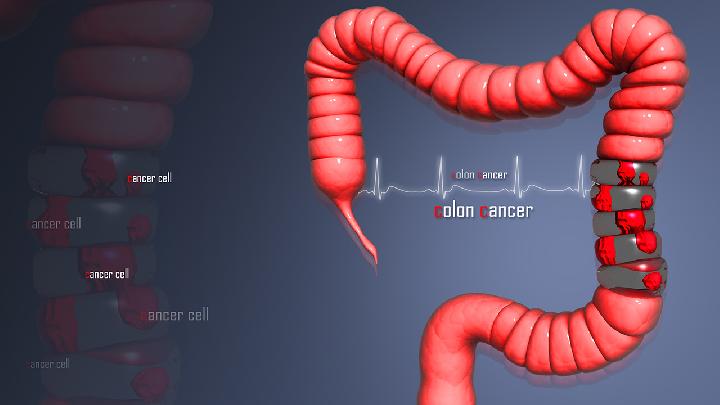

胆囊切除后预防大肠癌

肠道的其他慢性炎症也有癌变的可能,如溃疡性结肠炎,约有癌变。

肠道的其他慢性炎症也有癌变的可能,如溃疡性结肠炎,约有癌变。